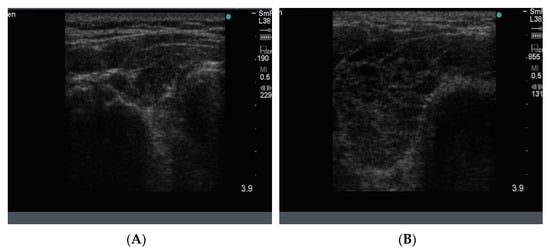

The normal gland does not contain any calcification. The presence of calcification in association with nodules generally indicates that the nodules are long standing and therefore likely to be benign. However, breaks in the wall of a calcified nodule suggest that the nodule is a cancer which has invaded into the surrounding thyroid tissue and is considered a suspicious feature of a nodule []. Calcification is sometimes seen as spots or sheets scattered throughout the thyroid. Calcification surrounding a thyroid nodule, giving it the appearance of a “bone ball”, can be felt as a hard, mobile lump on neck palpation that is crunchy on biopsy. Chronic linear or egg shell calcification is associated with shadowing because the ultrasound waves are unable to pass through calcified tissue (Figure 8A,B). Calcification is also seen in the thyroid of patients with chronic Hashimoto thyroiditis and Graves’ disease.

Figure 8.

In (A) linear calcification in the anterior aspect of a benign 15 mm nodule is seen as a curved bright hypoechoic shelf (arrow) that blocks the transmission of the ultrasound waves, so the nodule behind appears to be very hypoechoic, as in a cyst. In (B) is seen a small hypoechoic calcified nodule (upper arrow) and below it, a larger nodule with linear calcification in its anterior surface (lower arrow).